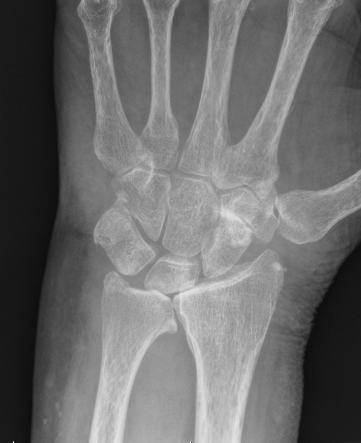

Xray

End stage rheumatoid arthritis of the wrist